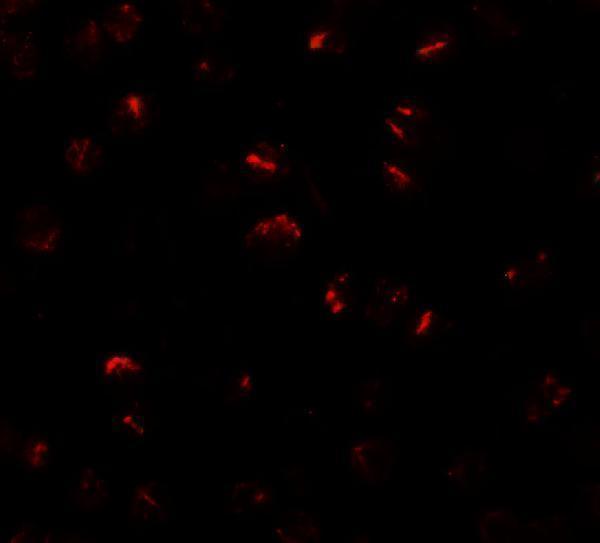

| Gene Name: | BMP15 |

BMP15; BMP-15; bone morphogenetic protein 15; GDF-9B; GDF9BODG2; Growth/differentiation factor 9B; POF4